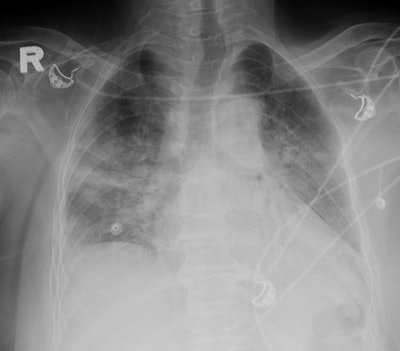

According to their previous research, Das and colleagues found 83% of initial chest x-rays showed lung parenchymal abnormalities in MERS-CoV. The main chest x-ray finding associated with MERS-CoV was ground-glass opacity (image above) in 66% of cases, followed by consolidation in 18%. Both ground-glass opacity and consolidation were apparent in 16% of cases. Less common radiographic findings included irregular linear-type airspace disease (9%) and multicentric cavitation (2%). The main findings can be seen in the two tables below.